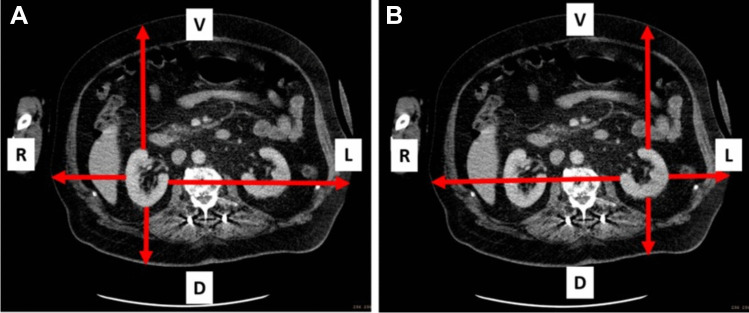

Procedures: A dedicated torso phantom with kidneys filled with a solution of 177Lu-PSMA was used for quantitative calibration of a SPECT-camera. The calculated sensitivity was adapted according to the individual attenuation of the patient in four directions from the kidney surface to the body surface (ventral, dorsal, left and right) obtained from a previously performed CT. A total of 196 patients undergoing 926 cycles of 177Lu-PSMA therapy were retrospectively analyzed. Abdominal SPECT was performed 24, 48 and 72 h after administration of 177Lu-PSMA including scatter and dead-time correction in every patient. Kidney dose was calculated using an individual attenuation-based procedure and compared to values from international literature.